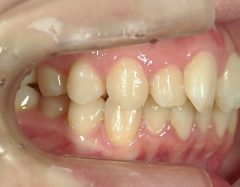

矯正歯科 治療後

no.8_8495_治療後_左.jpgno.8_8495_治療後_正面.jpgno.8_8495_治療後_右.jpg